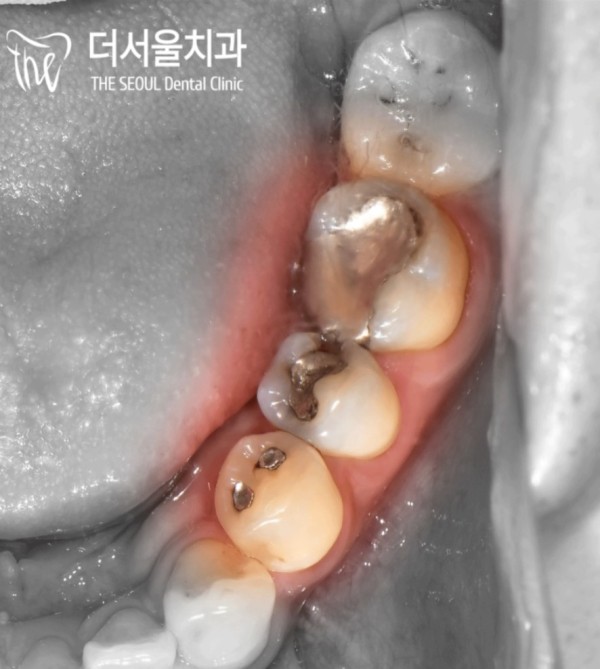

이렇게 아말감은 눈으로 보았을때 심미적으로

좋지는 않습니다. 수은이 포함된 재료답게, 은빛의 재료로 치료가 마무리되어 있는데요.

이 부분이 의심되었기 때문에 파노라마 사진으로 치아 속을 진단하기로 했습니다.

When you look at the amalgam with your eyes, it's aesthetically

It's not good. It's a material that contains mercury, and the treatment is finished with silver.

Since this part was suspected, we decided to diagnose the inside of our teeth with a panoramic picture.